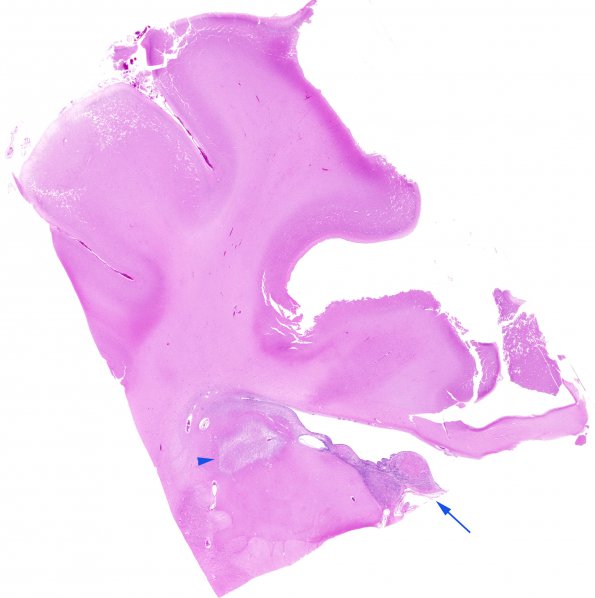

Washington University Experience | NEOPLASMS (GLIAL) | Subependymal Giant Cell Astrocytoma (SEGA) | 19B1Tuberous Sclerosis (Case 19) H&E N11 WM

19B1-3 This lesion (arrow, 19B1) shows a typical SEGA/SEN with pavement cells (H&E)